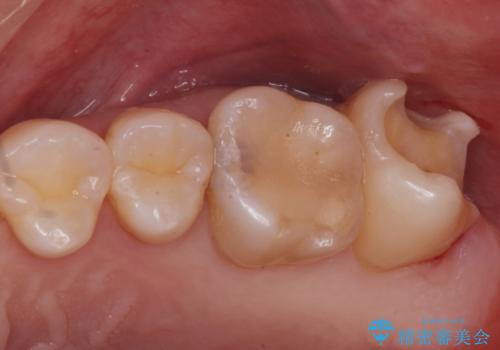

奥歯の治療の劣化が気になる。ザラザラしている

- 奥歯がザラザラして欠けている気がするとの事で来院。

古いプラスチックの詰め物がされていて、少し欠けていました。

拡大鏡下で古いプラスチックを除去して虫歯がないことを確認して

e-maxインレーにて治療しました。